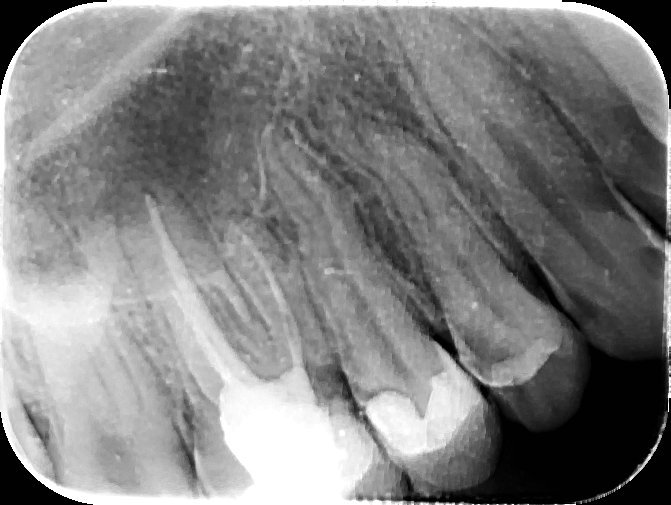

Дали някой може да ми каже има, ли нещо на шести зъб?

Имам записан час за вторник... Просто от началото на януари имам тъпа болка във всичките горни, а понякога и долни зъби. Бях на зъболекар, направих панорамна снимка и отидох като ми казаха, че е от венеца. Мажа се с пастичка и болката беше изчезнала (не знам дали е от това), но тази нощ се събудих от същата болка като преди, а още се мажа с тази пастичка и уж ми беше минало. Реших да снимам 6 зъб горе, който знаех, че е мъртъв, за да се види по-хубаво и да се види като вариант за проблема, който имам.